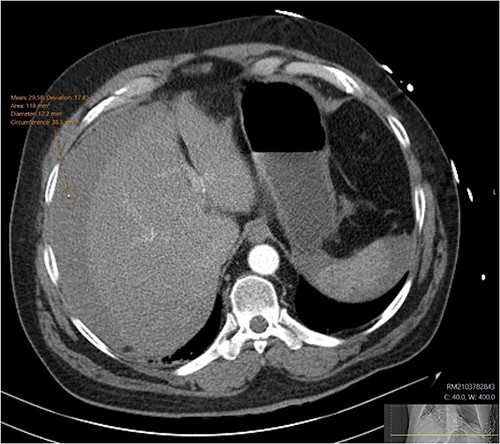

A CT abdomen-pelvis (CT-AP) revealed an acute haematoma inferolateral to the third part of the duodenum and another at the root of the mesentery. High density fluid related to the mesenteric bleed was also seen extending from the right para-colic gutter into the pelvis and in the peri-hepatic region. The patient was admitted under general surgery, stabilized with intra-venous fluid resuscitation, co-amoxiclav and metronidazole and cross matched for four units of blood. A CT-angiogram demonstrated acute haemorrhage throughout the abdomen with a 104 x 62 mm haematoma arising centrally at the level of L2 within the mesenteric fat (Fig. 1). The haematoma did not appear to originate from any specific mesenteric vessels but was related to some mid and distal jejunal loops. The angiogram also showed discontinuity when tracing the proximal and mid jejunal loops inferiorly, extensive haemorrhagic peritoneal fluid around the liver extending inferiorly (Fig. 2) and a small amount of peri-splenic haemorrhagic fluid. Curved reformatting of the angiogram revealed no abnormalities within the superior mesenteric artery (Fig. 3).

CT angiogram showing a large acute mesenteric haematoma. Figure 1 is taken from an axial section of the patient’s initial CT angiogram of the abdomen and pelvis. The arrow shown highlights an area of high-density fluid representing a 104 x 62 mm acute mesenteric haematoma.